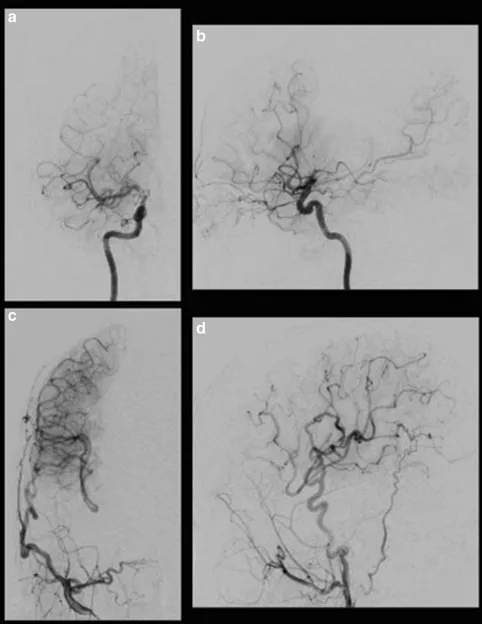

相比之下,对于春奈而言,早期的征兆发现及诊断在一定程度上帮助她避免了神经功能损伤。川岛教授为其进行了颞浅动脉-大脑中动脉STA-MCA双吻合术后,春奈没有出现谵妄、癫痫、头痛和新的神经功能缺损等并发症,术后5天和7个月MRI未见缺血性病变。MRA显示STA在7个月内有发展和扩张,选择性右颈外动脉造影显示右侧大脑中动脉区域有大量的血供。

图3:春奈的术后右颈动脉造影显示经右侧大脑外动脉的旁路血流通过MCA和ACA供应到灌注较少的区域。右侧颈内动脉正位(a)、侧位(b);右颈外动脉正位(c)、侧位(d)。